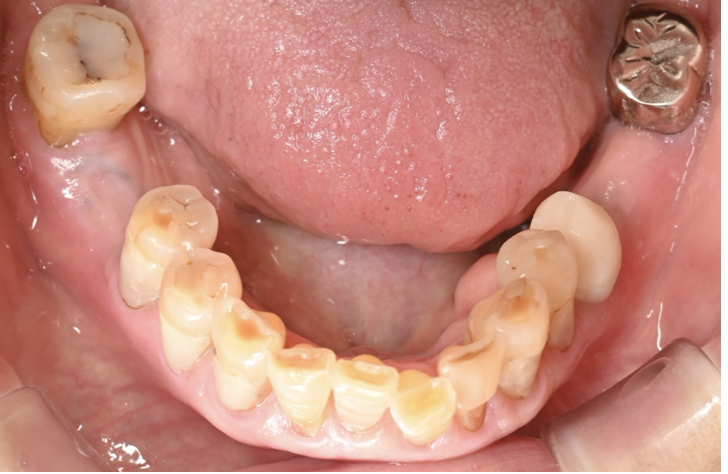

インプラント症例4

治療前

骨造成

治療後

| 年齢・性別 |

60代 女性 |

|---|---|

| 主訴 |

「左上奥歯にインプラント治療したい。」 |

| 治療内容 | 骨吸収が大きかったため、まず骨造成を行い、6か月後にインプラント埋入(ソケットリフト併用)を行った。 埋入後3か月後に上部構造(ジルコニア)を装着した。 |

| 治療期間 |

1年・15回 |

| 治療費用 | 総額:605,000円(税込) 【内容】 骨造成(GBR) 100,000円 インプラント埋入手術 270,000円 ソケットリフト 50,000円 インプラント被せ物 130,000円 |

| リスク・副作用 | ・外科処置が2回必要。 ・自費診療(保険適用外)となる。 ・骨造成後、腫れや内出血が起こる可能性がある。 ・ソケットリフト後、稀に上顎洞内感染の可能性がある。 |